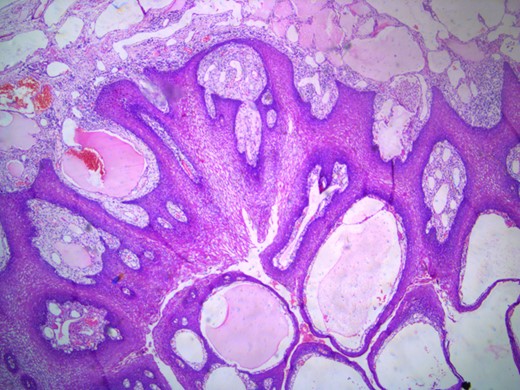

The histopathology report showed mucosa lined by stratified squamous epithelium, with underlying stroma showing dilated vascular channels lined by endothelial cells and containing red blood cells in their lumen confirming the diagnosis of lingual cavernous hemangioma as shown in Figs 5 and 6.

Microscopic appearance of the lingual cavernous hemangioma stained with eosin and hematoxylin at four times magnification.